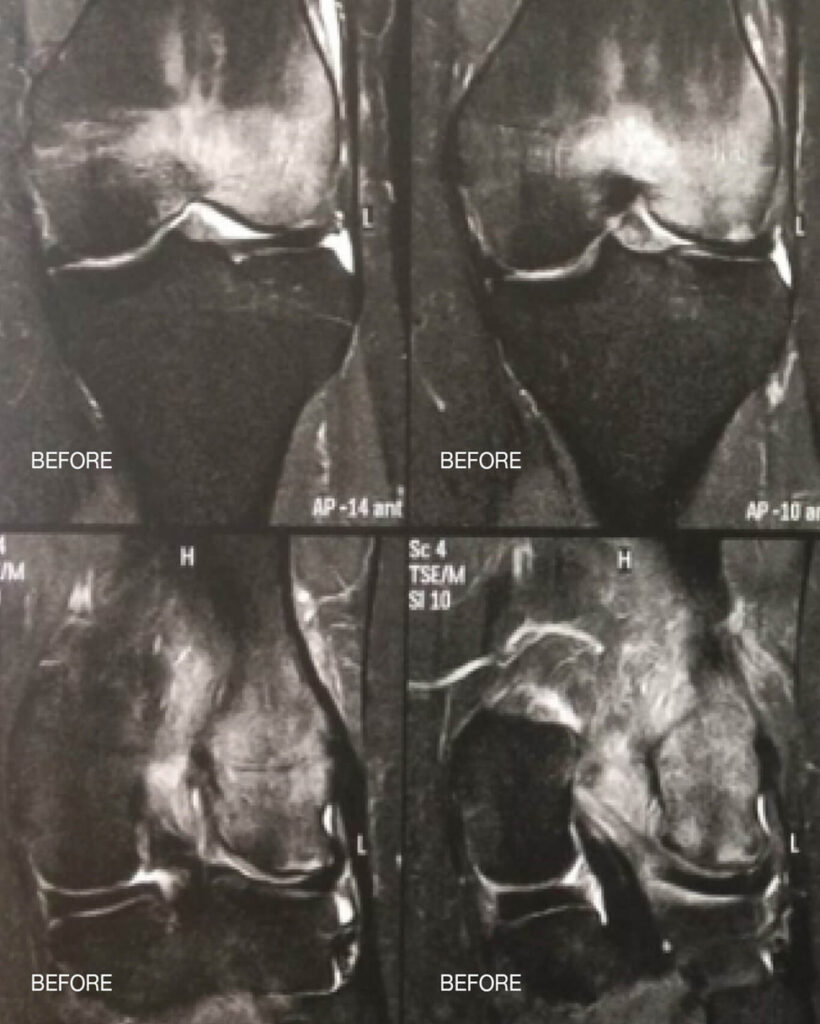

Las siguientes imágenes muestran un edema medular en la articulación de la rodilla antes y después de la terapia papimi. El tratamiento tuvo éxito tras sólo 10 sesiones.